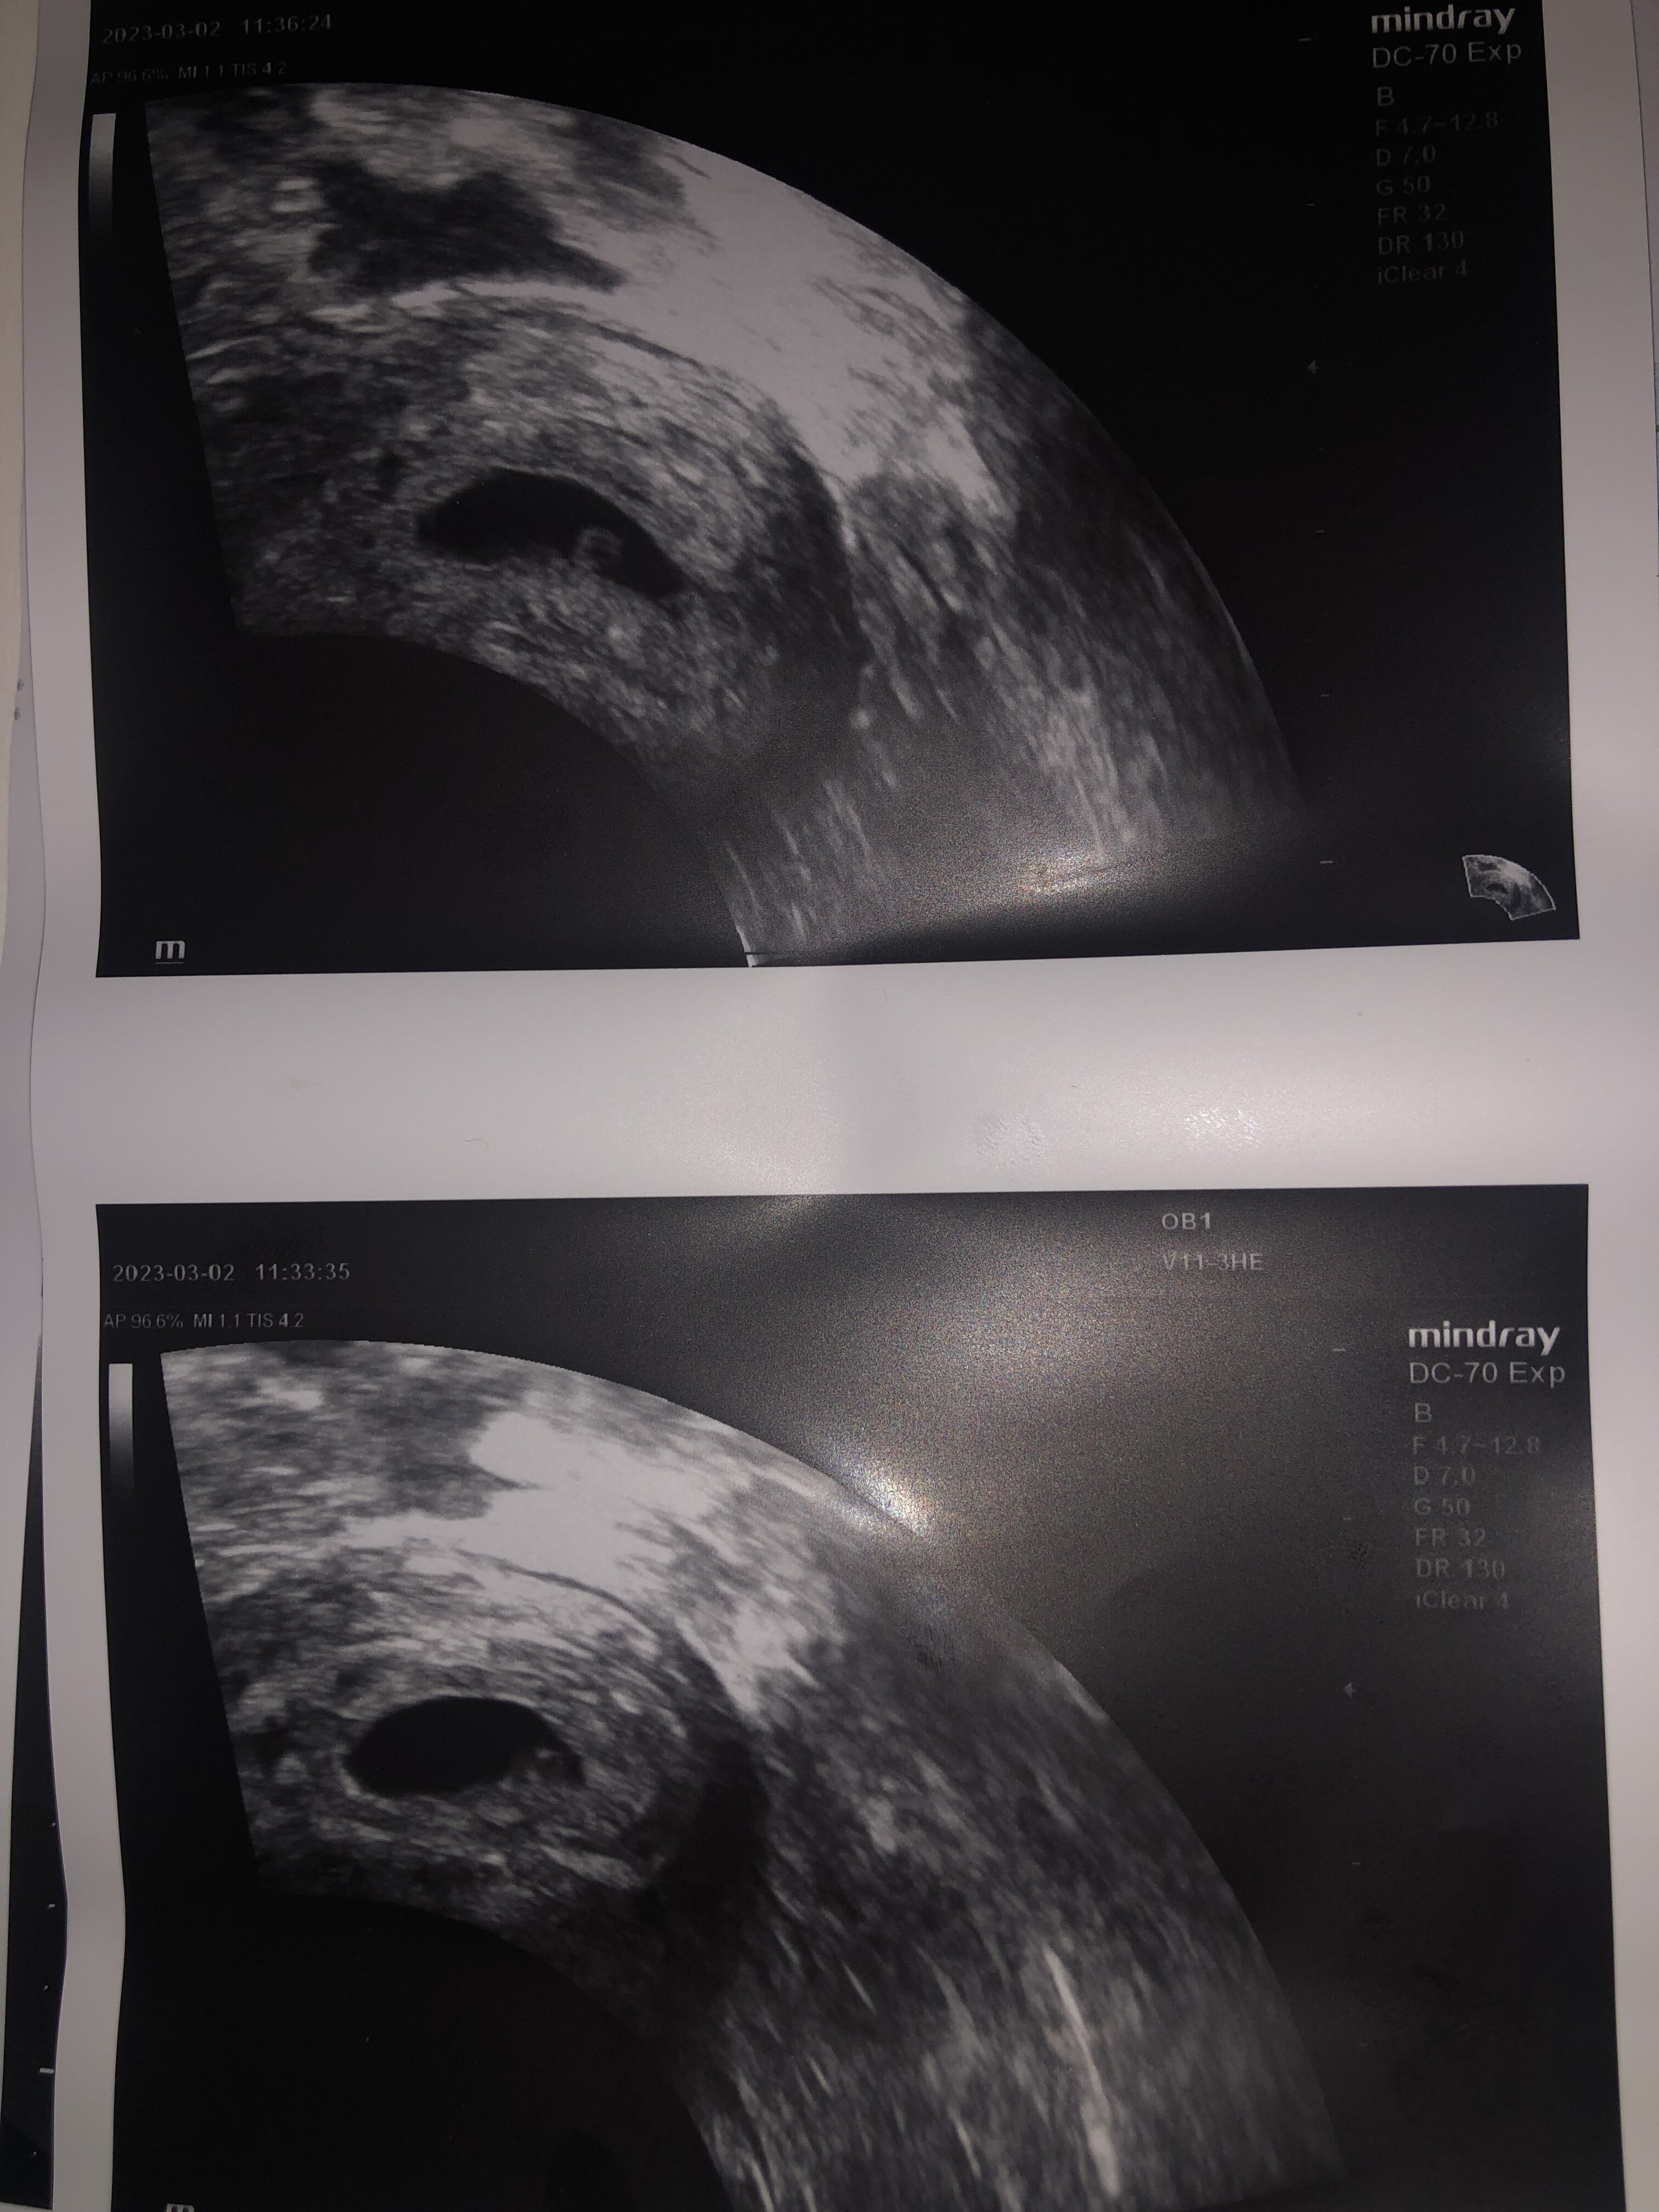

Hej dziewczyny. Byłam ostatnio na USG ciąża wydaje się być młodsza o jakiej 2tyg (przynajmniej z rozwinięcia No i z moich obliczeń - mam bardzo długie cykle 34/36 dniowe). Czy myślicie ze za tydzień będzie już widać zarodek? Dostałam taki wydruk ale lekarz nic mi więcej nie powiedział. 5 min i po wizycie